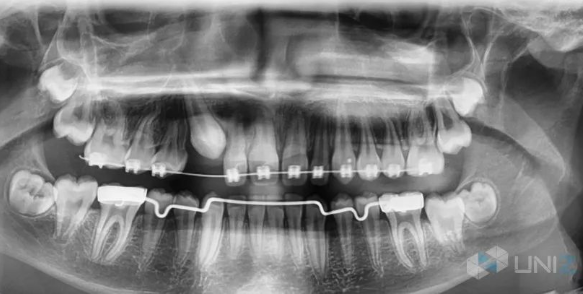

每個人都希望有一口整齊潔白的牙齒,越來越多的人選擇齒科正畸矯正。傳統的正畸矯正方式主要以鋼絲矯正器來治療,這種治療方式非常不美觀,口腔衛生護理較難,而且金屬矯正器可能會刮破嘴唇并造成感染。

隨著科技的進步,隱形矯正技術逐漸進入人們的視野。隱形矯正技術會根據每個人的不同牙齒結構進行量身定制,做出透明的隱形矯正牙套,隱形牙套維護方便,可自行摘戴,不影響社交、進食和運動。

學員可以學到從口腔掃描,到治療方案設計、3D打印牙模、熱吸塑成型牙套、后處理及佩戴的全套隱形矯正流程。該課程為期兩年,不光學習理論知識,還會親手進行實踐操作,最大特點是課程中既包含最新的隱形矯正教學方案,同時也包含傳統的鋼絲矯正教學,讓學員可以同時掌握兩種不同的矯正技術。

UNIZ科技的SLASH PLUS 3D打印機,憑借打印速度快,精度高等集成優勢,成為EOMAC現代正畸學院的首選正畸教具。其他3D打印機打印模型需要兩三個小時,學生無法當堂看到打印效果,更無法當堂利用打印的模型來做練習。但SLASH PLUS卻可以在13分鐘內快速打印出6個牙模,真正做到“當堂講課,當堂練習”,極大提升了學習效果和效率。